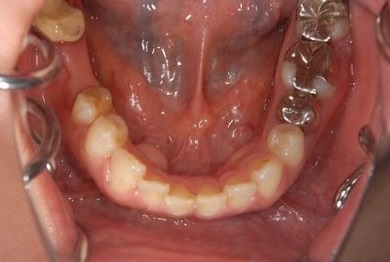

性別/年齢 女性 / 42歳

主訴 ブリッジが外れてしまった。

治療方針 セラミック治療にて審美的回復を行う。

治療内容 オールセラミッククラウン4本(オールセラミック用土台2本)

治療部位

2 1 1 2

総治療費 553,350円

治療期間 11ヶ月